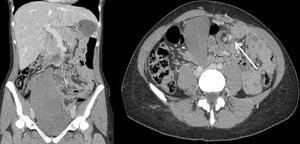

A 23-year-old patient came to the emergency room due to abdominal pain and the appearance of a large palpable mass. Abdominal CT scan revealed the spleen positioned in the pelvis, which was enlarged and showed signs of ischemia secondary to multiple loops at its vascular pedicle (Fig. 1). A midline laparotomy was performed, during which a very congestive 17-cm spleen was observed with infarcted areas and a twisted vascular axis (Fig. 2). Splenectomy was performed with ligation of the vascular pedicle, without incident.